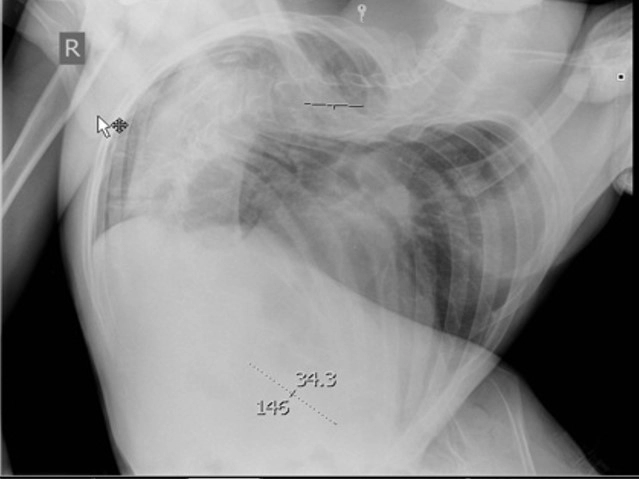

Физическое состояние пациента

Обеспечение проходимости дыхательных путей – недостаточное разгибание шеи